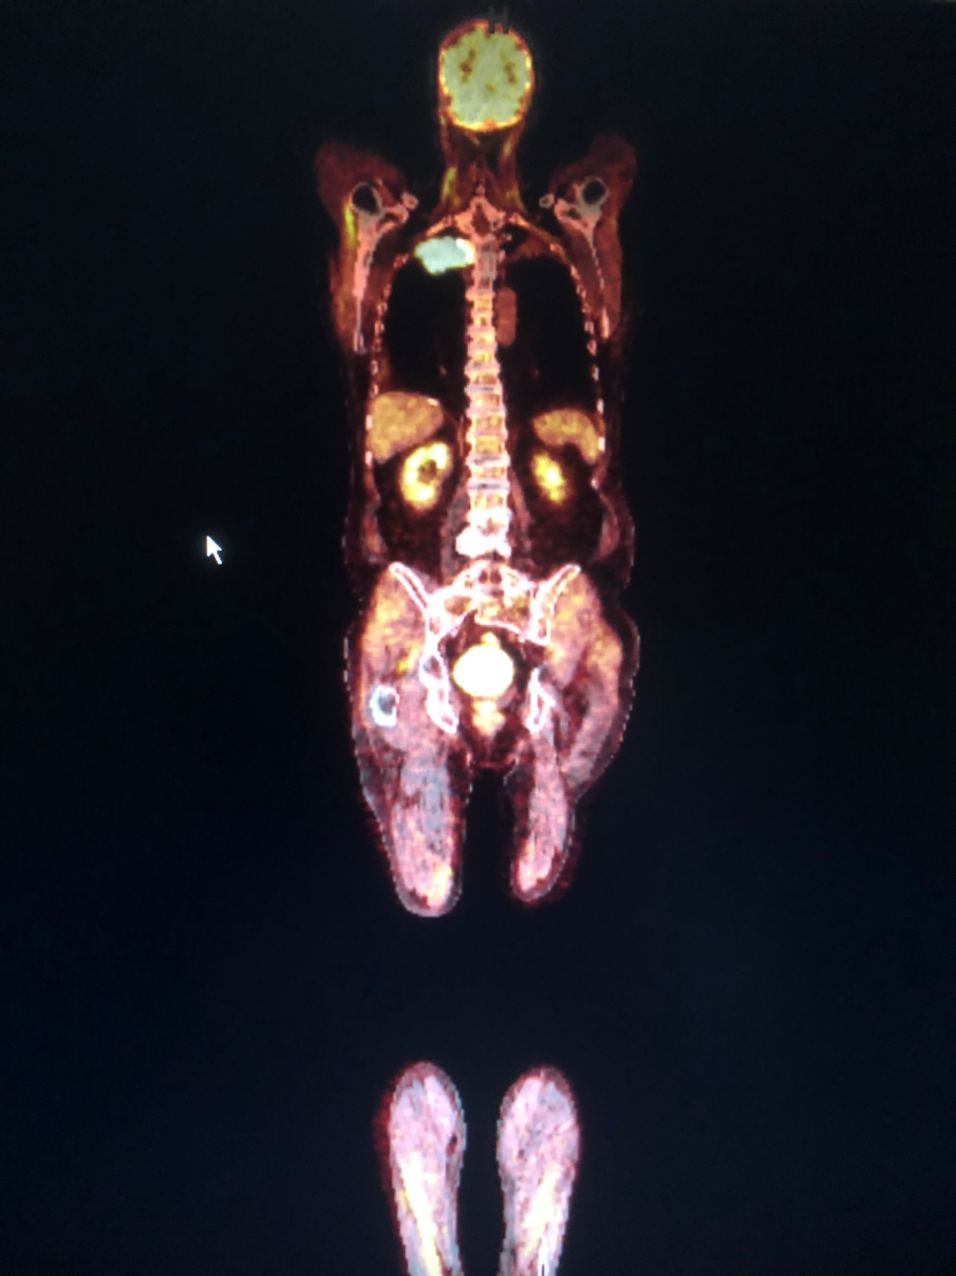

Помогите пожалуйста оценить, норм тут все или нет? Мне кажется тут неполное покрытие чашки эндопротеза

Никогда ещё не приходилось оценивать эндопротез 🙈